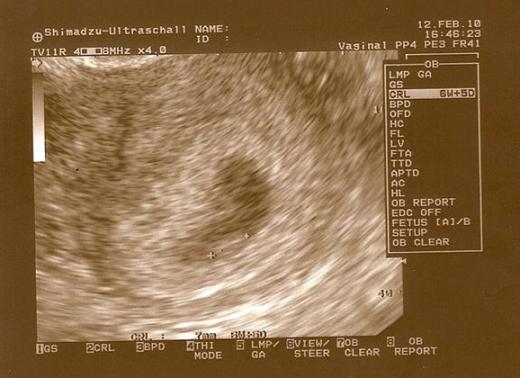

Ogolnie musze juz leciec do szpitala ale chcialam szybko wkleic wam najnowsza foteczke mojego bobaska!

8 tydzien i 2 dni :tak: Widac juz raczki i nozki :-D

• DSC01394.jpg

DSC01394.jpg

27,9 KB · Wyświetleń: 171

:) był pęcherzyk, echo zarodka i bijące serce:) Z CRL wychodzi równe 7 tygodni, moim zdaniem ciąża jest kilka dni starsza, ale w poprzedniej też mi pokazywało młodszą:)